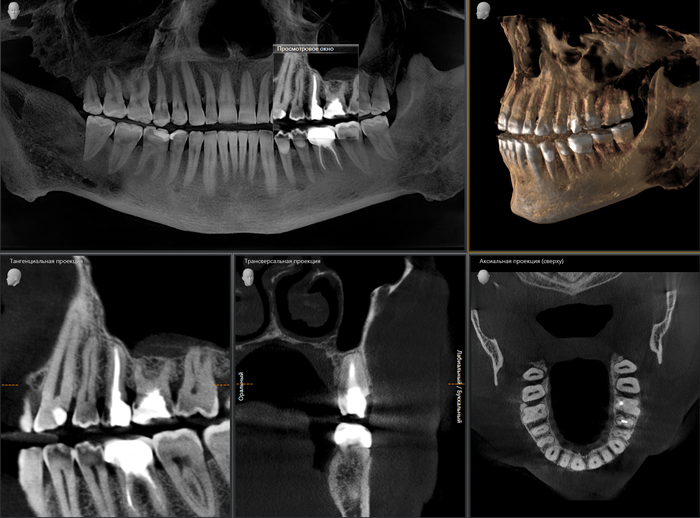

На компьютерной томографии четко видно, что есть провал в области отсутствующего зуба.

Эта компьютерная томография была сделана до того, как зуб окончательно развалился.

Что мы видим?

Верхняя левая 5-ка, не подлежащая ни терапевтическому, ни ортопедическому лечению. Что делаем? Правильно — удаляем зуб и вкручиваем болт.